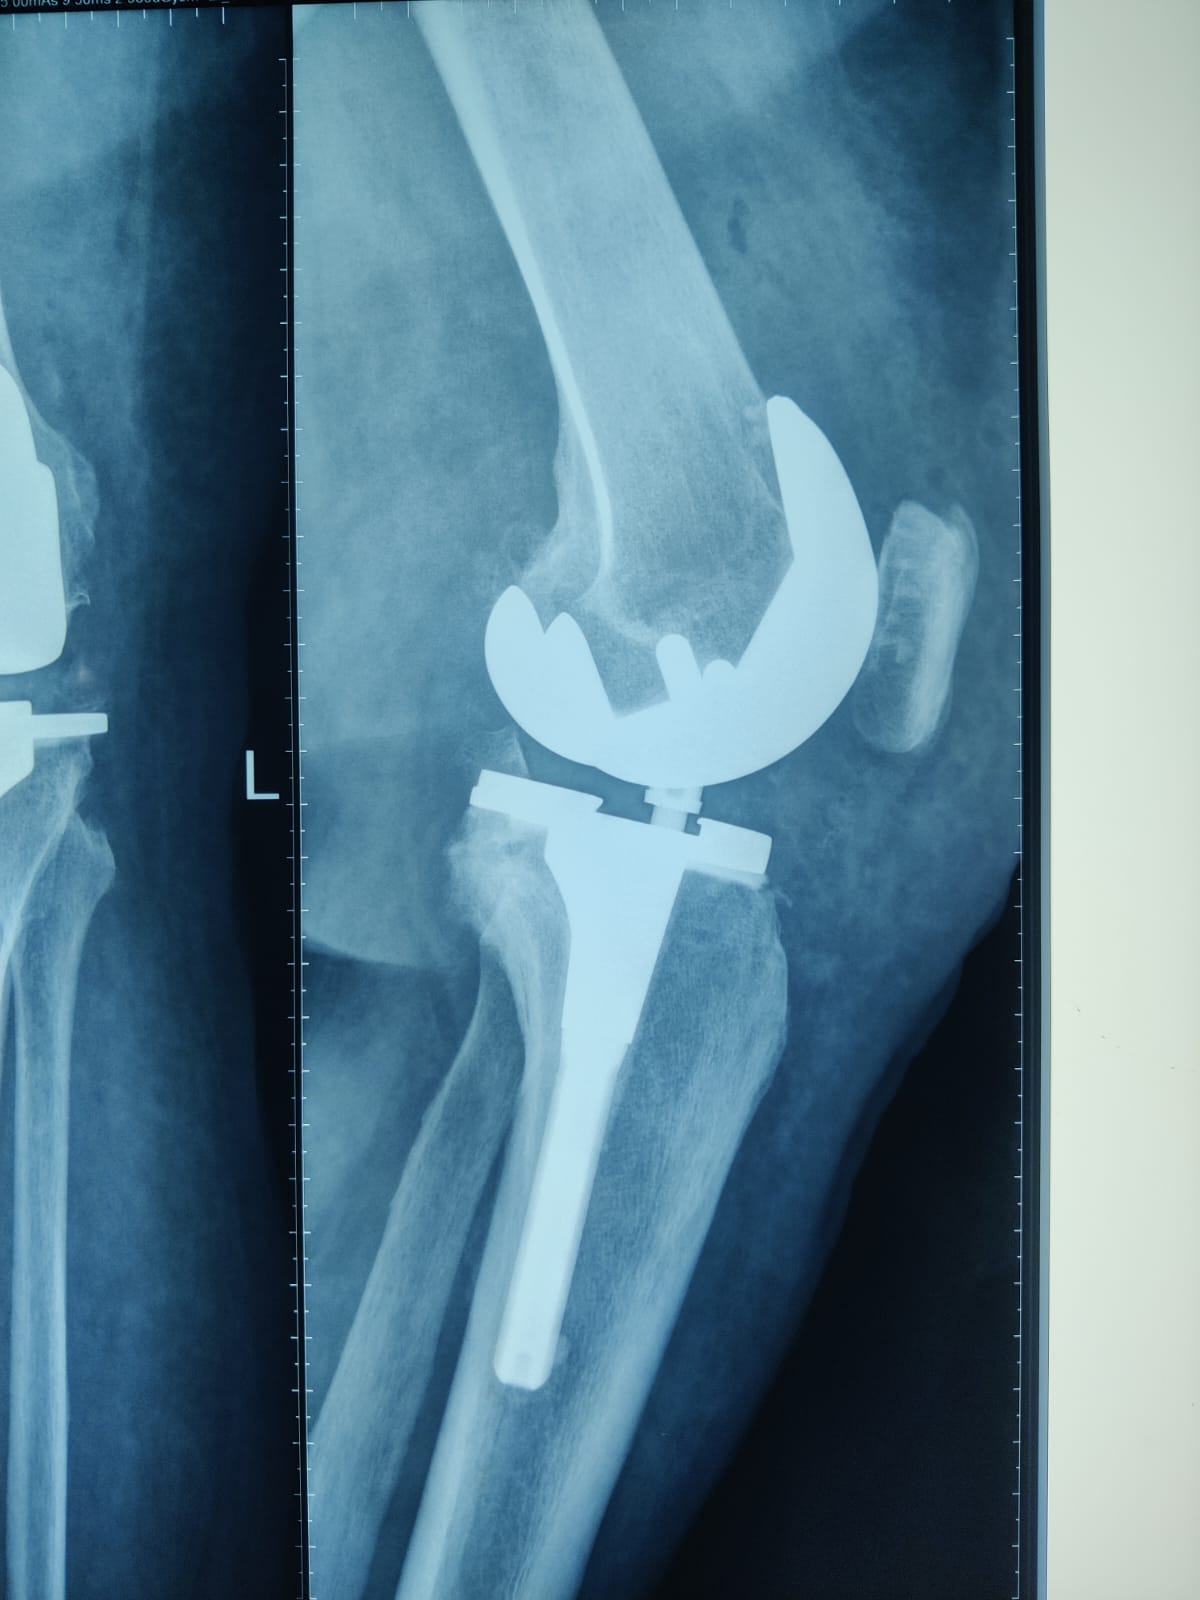

62 year old female with stage 4 OA

Primary Left TKR

Post op images of Right knee